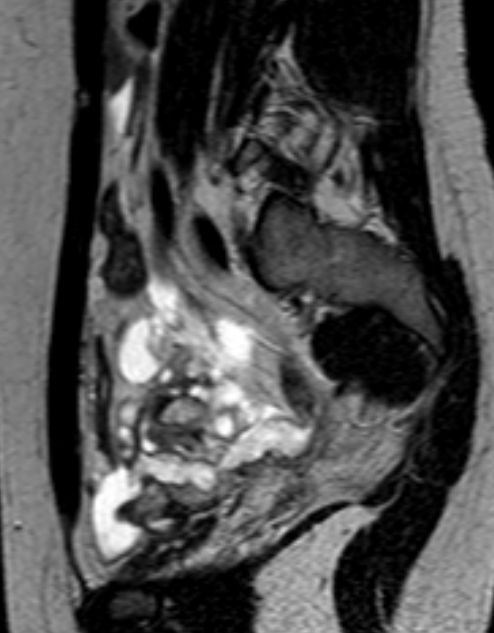

Pseudomyxoma peritonei 26-jährige Frau mit Tuboovarialabszess. Bei der Laparotomie fanden sich zahlreiche knotig-glasige Veränderungen im Peritoneum des Mittel- und Unterbauches sowie beidseits zystische Ovarien. Histologie: Pseudomyxoma peritonei (low grade). Dieses entsteht in den meisten Fällen auf dem Boden einer muzinösen Neoplasie des Gastrointestinaltraktes, insbesondere der Appendix. Die Ovarien dürften sekundär in den Prozess einbezogen sein.